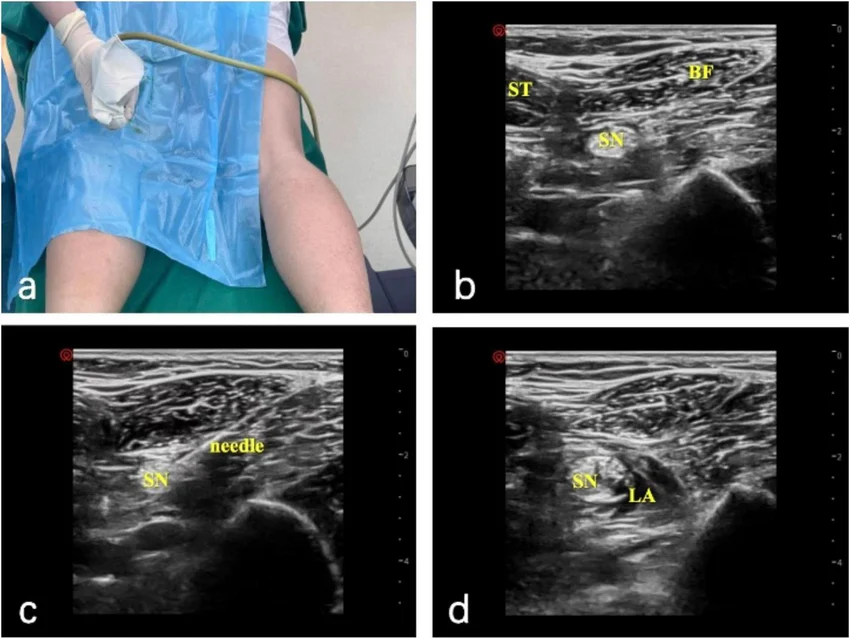

Dr. Collins refuses to push Morphine as requested by Dr. Garcia, citing the risk of clouding the patient's mental status before a definitive neuro exam and Head CT can rule out intracranial pathology. They opt for a regional Popliteal Nerve Block using Marcaine, which will provide localized anesthesia to the lower leg without systemic sedative side effects.

- Ultrasound-guided Popliteal Nerve Block with Marcaine

Block is completed. Takes ~10 minutes for full effect. Patient begins to calm down, allowing for safer transport to CT.